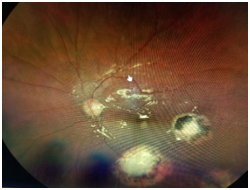

Dilated fundus examination revealed that the right eye was unremarkable, yet the left eye showed several punched-out-chorioretinal lesions with macular involvement (Figures 1&2). The OCT (Figures 3&4) depicts a normal right eye with abnormal left eye showing macular edema precipitated by vascular damage, ischemia, and inflammation leading to blood-retinal barrier breakdown and impaired fluid filtration from the POHS. The OCT also shows macula edema and a neovascular membrane of the left eye. Due to the current findings, the retina referral was initiated with confirmation of the diagnosis of POHS with treatment of Avastin (bevacizumab)1.2 mg. Three months post-op, best visual acuity in the left eye was 20/70 and the primary condition of POHS was stable yet intraocular pressure was present at 35mm Hg in the left eye. The right eye was within normal limits and had a intraocular pressure (IOP) of 12mm Hg. Cup to disc ratios were recorded at 0.25/0.25 in the right eye and 0.75/0.75 in the left eye. The visual field confirmed optic nerve damage and a superior arcuate scotoma (Figure 5). The patient was treated with simbrinza 1%/0.2% two times per day in the left eye. After two weeks the pressure was stabilized at 15mm Hg in the left eye with right eye pressures remaining unchanged.

Figure 2 The left eye (OS) shows several punched-out-chorioretinal lesions with macular involvement.